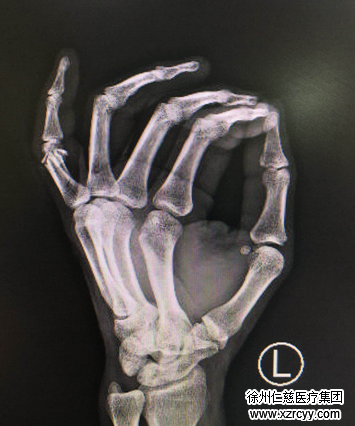

经检查,患者刘刚虎左手小指近节畸形,近节背侧见一横行切口,约3cm,伤口深达骨质,创缘不齐,骨头碎得比较厉害,挫伤污染重,伤口内见肌腱骨折断端外露。胡俊生医生手术小组立即为其清创,固定骨折端,缝合修复拇指伸肌腱及皮肤,并最后进行了外固定。手术进行约2个小时,一切顺利。

我手指因工作受伤骨折,市内二大医院以无病床只简单包扎,拒之门外,只好把侥幸心情寄到必威官方首页官网betway。时已黄昏,医生已要下班,手外科四区胡俊生主任、孔维康医生看此情景,二话没讲,立即开通绿色通道,安排护理人员快速送做X光线,化验检查。确定无明显手术禁忌症后,急把我送手外科四病区手术室。胡主任、孔医生已早等候,做好手术的准备。